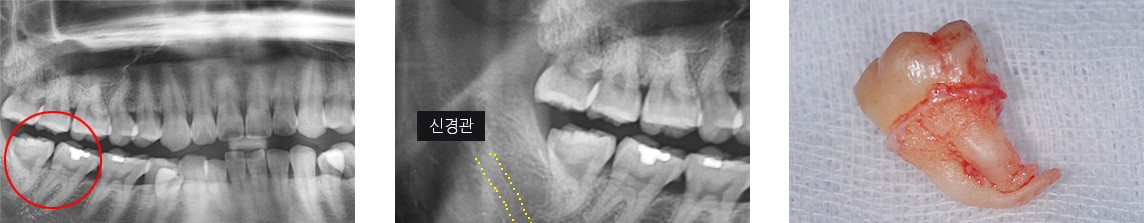

사랑니 발치는 일반 진료가 아닌 외과 수술입니다. 사랑니는 치아 모양과 방향 모두 제 각각 이기 때문에 턱 주변 조직과 치아 뿌리의 방향,

신경관 위치 등을 모두 고려해야 하는 고난이도 진료입니다.

사랑니가 잇몸 속에 누워 자란 경우 주변 신경관에 영향을 줄 수 있어 충분한 노하우로 안정적으로 발치를 해야 합니다.